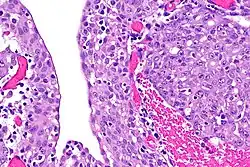

| Renal medullary carcinoma (right of image), reactive urothelium and sickled red blood cells. H&E stain. | |

The finding that virtually all people affected by renal medullary carcinoma carry at least one copy of the HbS mutation suggests that sickle cell trait somehow predisposes to this type of cancer.[5] The precise mechanism is unknown, but red blood cells with a sickle cell configuration have been identified in pathology specimens.[2]

The diagnosis of renal medullary carcinoma is typically made after individuals with sickle cell trait present with the typical signs and symptoms outlined above, in combination with radiographic imaging (usually abdominal/pelvic CT scan) studies and ultimately surgical biopsy and pathological examination of the tumor. Findings on radiographic examination are non-specific and can reveal a mass deep within the kidney.[6] Histopathology studies show a distinctive pattern that can be distinguished from other renal tumors.[1]